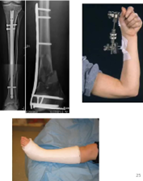

16

Q

Vad ser du på bild, vad är felet?

A

• Vänster humerusfraktur har mkt callus men den dockar inte ihop är tecken på att den behöver stabilitet. För mkt strain

o Hypertrof pseudartros

• Radiusfraktur till höger där det inte händer något. För dålig mekanisk stabilitet och för lite biologi. Usel strain på radius med det de satt in (räcker inte)

o Atrofisk pseudartros